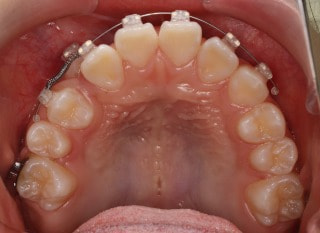

前歯装置装着時